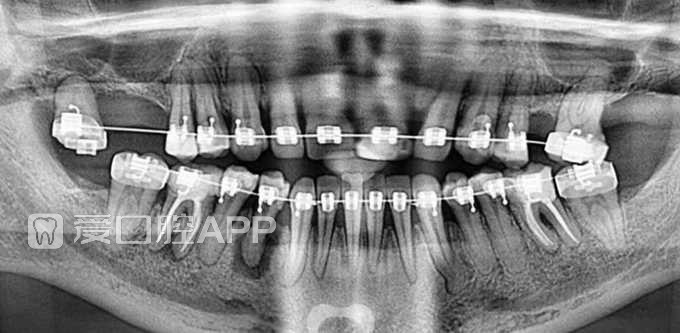

看个根充 —— 右下4

by Pablo Aparicio